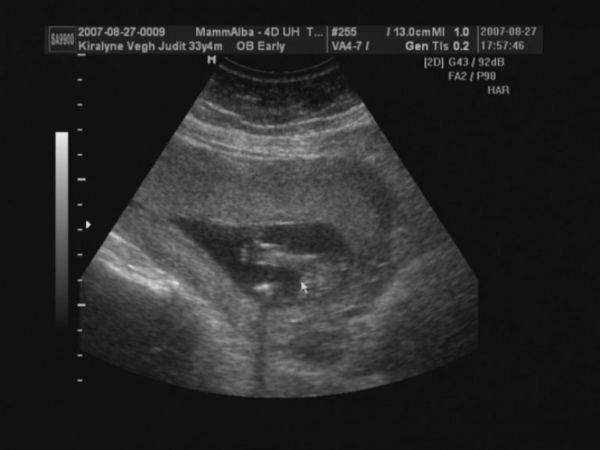

Megjöttünk 4D-ről.

CRL 9,54

BPD 2,83

A gép 14+6 napra dobta ki a korát, ami jó is.

Pulzus 167 percenként

Jelenleg kuki nem látható. Szóval remény még mindig van.

alsónézet, itt kellene lennie a kukinak.

A feneke és a lábacskái látszanak.

2D oldalról